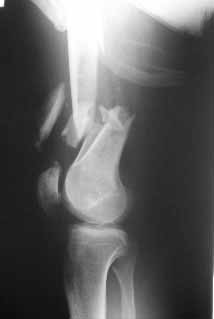

What would be your method of choice to fix this Gr IIIa open high energy supracondylar femur fx, neuro vasculary intact. 30YO male MBA hemodynamically stable, no chest injuries. Right temporal bone fx, no IC bleeding on the head CT. Images attached.

Date: 10/31/2004, 12:13 From Zsolt Balogh @ http://weborto.net/ Dear Alex, This is what we have done... As generally true for LISS look at the bone

not the hardware. There are two more screws above. The one not completely

in got damaged head. Zsolt